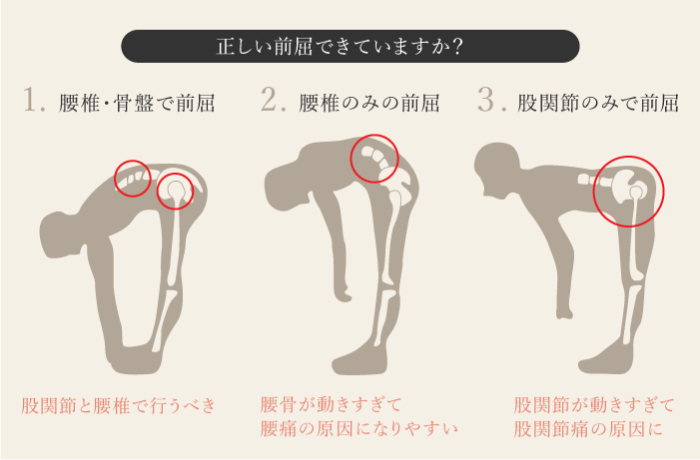

腰を曲げる動作が原因

腰椎が後方にシフトしてしまっているために症状がでます。

腰を反る動作が原因

腰椎が前方にシフトしてしまい椎間関節などに症状がでる。

腰を後ろに反らしたり、仰向けに寝ていると痛みが出ることがある。